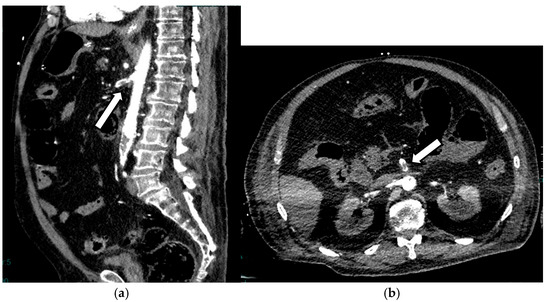

Acute mesenteric ischemia (AMI) is a clinical condition caused by vascular insufficiency, resulting in intestinal damage. Is often underestimated, if not driven by clinical suspicion, due to the non-specific clinical symptoms (usually represented by acute abdominal pain) and the absence of reliable markers, which results in a poor prognosis and high mortality. We can identify three main forms of AMI: arterial, venous, and non-occlusive. Arterial AMI is the most frequent form, caused by occlusion of the superior mesenteric artery or one of its branches. Venous AMI is the least frequent, caused by thrombosis of the superior mesenteric vein or its branches. Non-occlusive AMI is due to a state of hypovolemia, which is frequent in patients who have undergone surgery. Given the difficulty of diagnosis based on the clinic alone, the radiologist plays a central role in identifying radiological signs of intestinal ischemia and in avoiding misdiagnosis. The radiologist’s role is mainly to identify factors predictive of necrosis, which allow us to stratify patients and direct them towards the proper management. The aim of this review is to provide indications for an adequate CT protocol, including an unenhanced phase, an arterial phase, and a venous phase, as well as to underline the features to investigate in the different forms of AMI, in order to increase the diagnostic capacity in this challenging disease. Full article

Show Figures

Figure 1